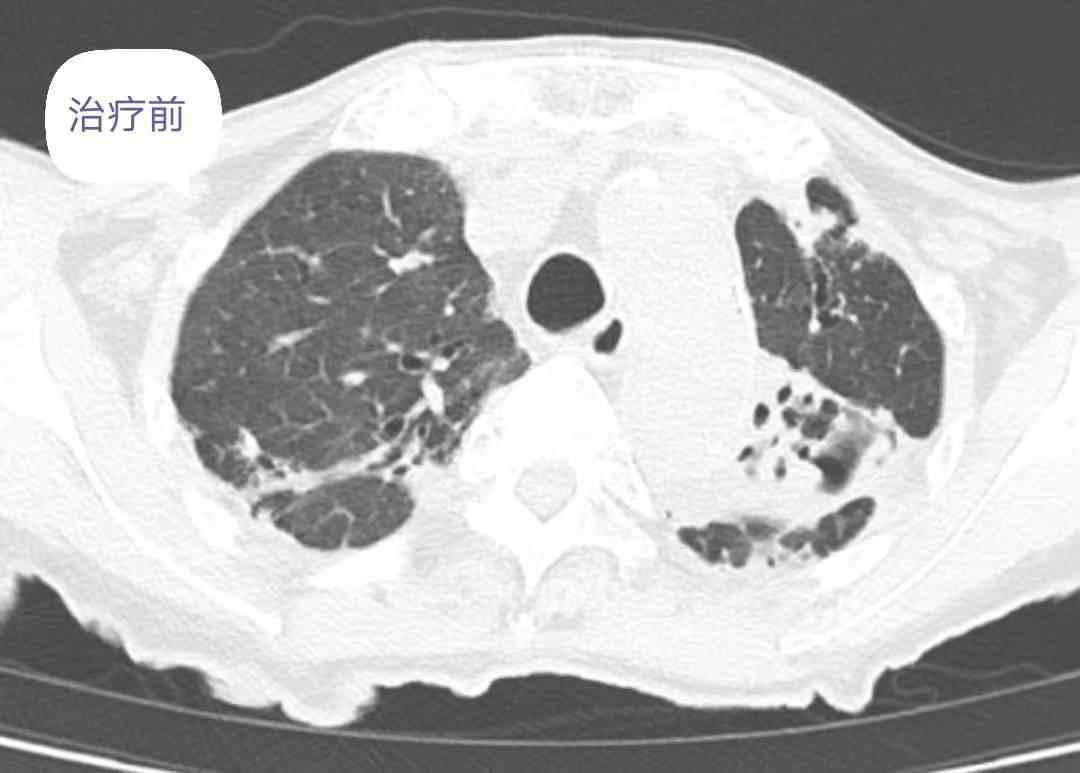

(3)辅助检查(2019.05.15)胸部CT报告:双肺气肿、支气管扩张伴感染,余双肺少许纤维性病灶血常规:WBC 11.82*109/L,N 9.08*109/L,N% 76.7%。炎症指标:CRP 56.1mg/L。PCT 0.05。血沉 123 mm/h。生化检查:白蛋白 31.8g/L,血糖、肾功能、心肌酶、电解质、凝血四项正常。尿粪常规正常。肿瘤标志物:CA199 260.37IU/ml,CA125 111.3U/ml,细胞角蛋白 4.68 ng/ml,AFP、CEA、NSE大致正常。痰细菌、真菌、结核菌涂片阴性。痰细菌、真菌培养阴性。

复查胸部CT:对比前片提示双肺感染灶减前吸收,肺气肿、支气管扩张,肺底少许纤维性病灶。患者病情改善后办理出院,随访期间未诉特殊不是。

基本病理改变是肺部炎性病灶及单发或多发的薄壁空洞,而纤维硬结灶、球形病变及胸膜渗出相对少见。病变多累及上叶尖段和前段,尤其是高分辨cT可清楚显示NTM肺病的肺部病灶,可有结节影、斑片及小斑片样实变影、空洞(尤其是薄壁空洞)影、支气管扩张、树芽征磨玻璃影、线状及纤维条索影、胸膜肥厚粘连等表现,且通常以多种形态病变混杂存在,由于NTM病程较长、肺组织破坏较重及并发症的存在。

4).影像学检查:往往提示肺部炎症病变,可表现为结节状、片样实变、空洞和纤维条索状,多位于双肺上叶和下叶,支气管扩张多位于右肺中叶和左肺上叶舌段,还可以表现出树芽征和磨玻璃样影。

1).诊断根据病史、临床表现、体征、实验室检查,可作出包括病因、病机、病理、并发症的完整诊断。有以下表现提示:非结核分枝杆菌肺病有咳嗽、咳痰、气促等症状明显。出现双肺呼吸音粗,双肺可闻及大量湿性啰音,未闻及干性啰音及胸膜摩擦音。抗TB抗体(–),PPD 试验(–),G试验、GM试验、新型隐球菌荚膜抗原测定均阴性;痰真菌涂片阴性、痰真菌培养阴性。肺功能:存在极重度限制性通气功能障碍;。胸部CT报告:双肺气肿、支气管扩张伴感染,余双肺少许纤维性病灶痰抗酸染色涂片检出抗酸杆菌,痰培养结果汇报提示:非结核分枝杆菌(龟分枝杆菌或脓肿分枝杆菌)。